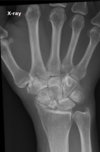

Fratura de Chaffeur

Fratura do processo estilóide do rádio.